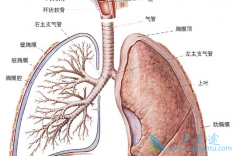

目前含铂双药化疗仍是 晚期肺鳞癌 的标准一线治疗方案,但此方案失败后病人没有太多好的选择。EGFR的过度表达或基因扩增已被发现是肺鳞癌的潜在驱动因素,对这部分患者来说,哪一种针对EGFR靶点的靶向药物效果更好呢?在保证效果的同时,如何选择更便宜 ...

肺鳞癌 占肺癌患者30%-40%的比例,与腺癌、小细胞肺癌一起组成肺癌三大亚型。而肺鳞癌患者的治疗却远远没有腺癌走运,有治疗价值的基因突变很少。但并不代表没有可用药物,那鳞癌患者有哪些靶向药物可以使用呢?效果如何呢?下面就来了解一下。1.阿法替 ...

有关统计表明, 特发性肺纤维化 患者自疾病诊出后的中值存活时间仅2~5年,5年存活率只有20%。特发性肺纤维化目前尚无肯定显着有效的治疗药物,根据近年来的随机对照临床试验的结果,结合我国临床实际情况,可以可以酌情使用的药物有以下几种。(1)吡非尼 ...

非小细胞肺癌一旦出现脑实质或软脑膜转移,患者的预后就会变的很差,如不治疗生存期就只有3个月,并且患者的生活质量也会大打折扣。而脑转移在EGFR突变的患者中更容易发生,发生率约40%。常规化疗药入脑能力差,现阶段主要通过靶药入脑的能力来解决问题 ...

特发性 肺纤维化 (IPF)目前尚无肯定显着有效的治疗药物,根据近几年来的随机对照临床试验的结果,结合我国的实际情况,可以酌情使用一些药物进行治疗。下面就整理了一些特发性肺纤维化主要使用的非药物治疗方法:1.戒烟:大多数特发性肺纤维化患者是吸 ...